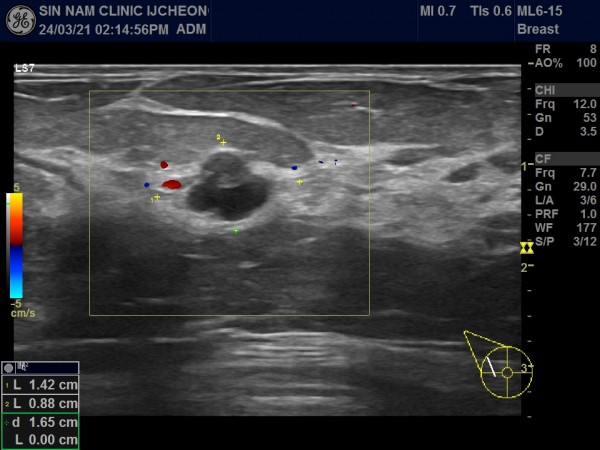

아래 사진 자료의 환자분은 50세 여성으로 국가검진으로 본원에 내원해주셨습니다.

유방촬영中 혹이 발견되어 초음파 검사를 시행하였습니다.

혹이 1.5cm 정도였습니다.

만져지거나 분비물이 나오는 증세는 없었습니다.

혹의 유두에 근접해 있고, 유관과 연결되어 있어 혈류가 증가된 소견이여서 유방암보다는 관내유두종의 가능성이 높아 대학병원으로 전원해 조직검사를 시행해서 관내유두종으로 진단받고 수술하셨습니다.